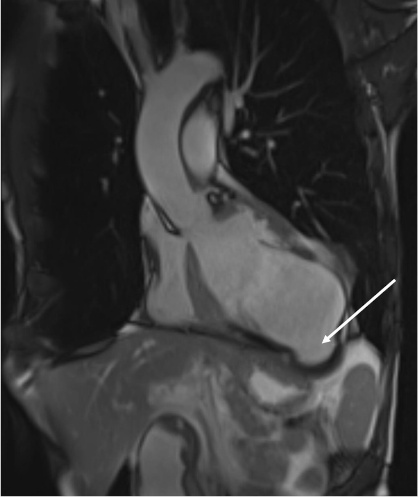

He underwent a right and left heart catheterization, which demonstrated 70% stenosis of his first diagonal vessel, 90% stenosis of his second diagonal vessel, and a second marginal artery, which was fully occluded at its ostium. Finally, a CMR was obtained, which was consistent with a large pseudoaneurysm measuring 8 × 7 × 5 cm containing lateral wall rupture (Figure 1, Figure 2, Figure 3). Within the pseudoaneurysm, a mural thrombus was present, measuring 2 cm in thickness.